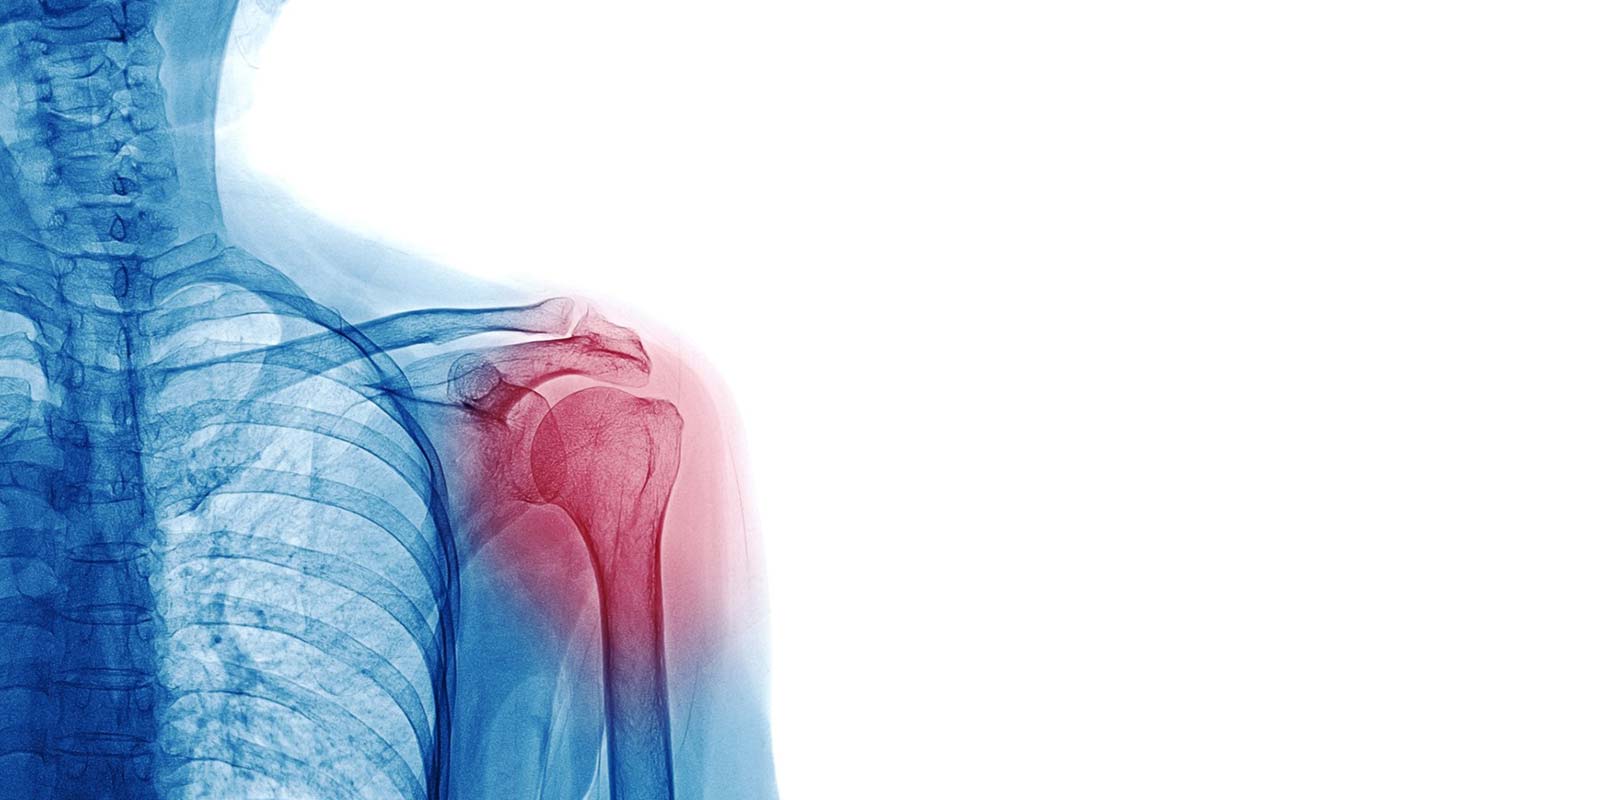

Ein wesentlicher Schwerpunkt unserer Praxis in der Rheintorklinik Neuss bildet die konservative (nicht-operative) und operative Behandlung funktions- und schmerzbeeinträchtigter Schultergelenke.

Von der Untersuchung und Beratung über die Behandlung mit ggf. Operation bis hin zur Nachbehandlung und Rehabilitation begleiten wir Sie durchweg. Die gesamte Behandlung bleibt somit in einer Hand, das schafft Vertrauen. Ziel ist es immer, soweit sinnvoll, die konservativen Therapieoptionen auszuschöpfen und eine Operation zu vermeiden. In unserer Praxis können wir alle gängigen konservativen Therapien wie z.B. Infiltrationen, Stoßwellentherapie etc. anbieten. Trotz der Vielzahl an durchgeführten Schulteroperationen ist es uns ein besonderes Anliegen, dass die meisten Schulterbeschwerden konservativ zur Ausheilung gebracht werden können.

Sollten sich Patient und Behandler gemeinsam zu einer operativen Therapie entscheiden, können wir den Eingriff mit allen modernen offenen und arthroskopischen (minimal-invasiven) Verfahren und Techniken vor Ort in den Räumlichkeiten der Rheintorklinik sowohl ambulant als auch stationär anbieten. Soweit möglich und sinnvoll, werden alle Eingriffe komplett minimal-invasiv durchgeführt.